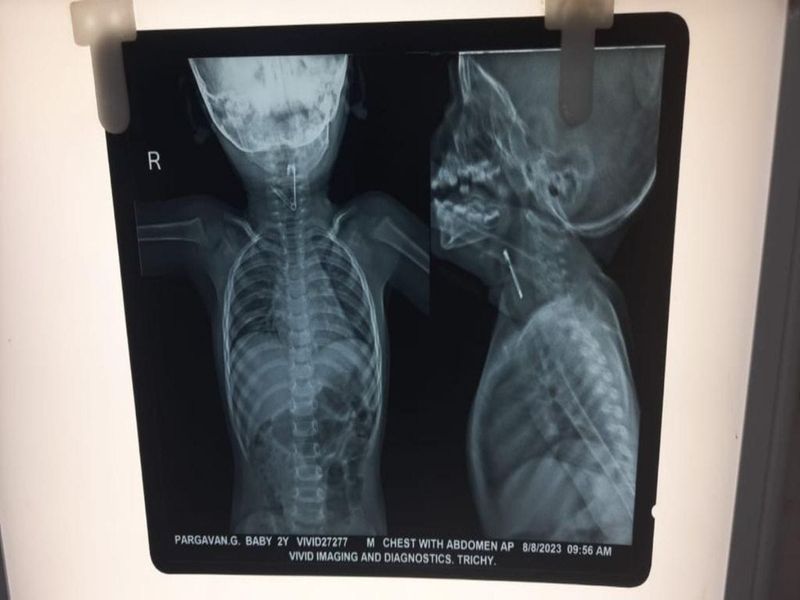

அப்போது திருச்சி அரசு தலைமை மருத்துவமனையில் உள்ள குழந்தைகள் சிகிச்சை பிரிவில் குழந்தையை எக்ஸ்ரே எடுத்து பார்த்த போது தொண்டை பகுதியில் ஊக்கு திறந்து இருப்பதனை மருத்துவர்கள் கண்டுபிடித்தனர். இதனை அடுத்து திருச்சி மகாத்மா காந்தி நினைவு அரசு மருத்துவமனையில் உள்ள காது, மூக்கு, தொண்டை துறையின் தலைமை மருத்துவர் அண்ணாமலை தலைமையிலான மருத்துவ குழுவினர் உடனடியாக குழந்தைக்கு மயக்கம் கொடுக்கப்பட்டு டியூப் வாயிலாக ஊக்கை வெளியே எடுத்தனர்.